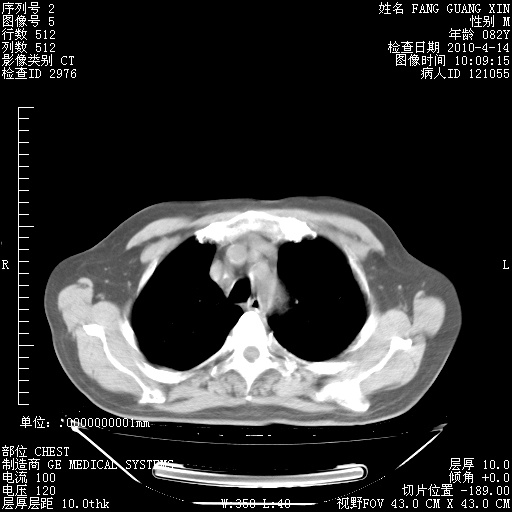

肺部CT平扫未见异常。